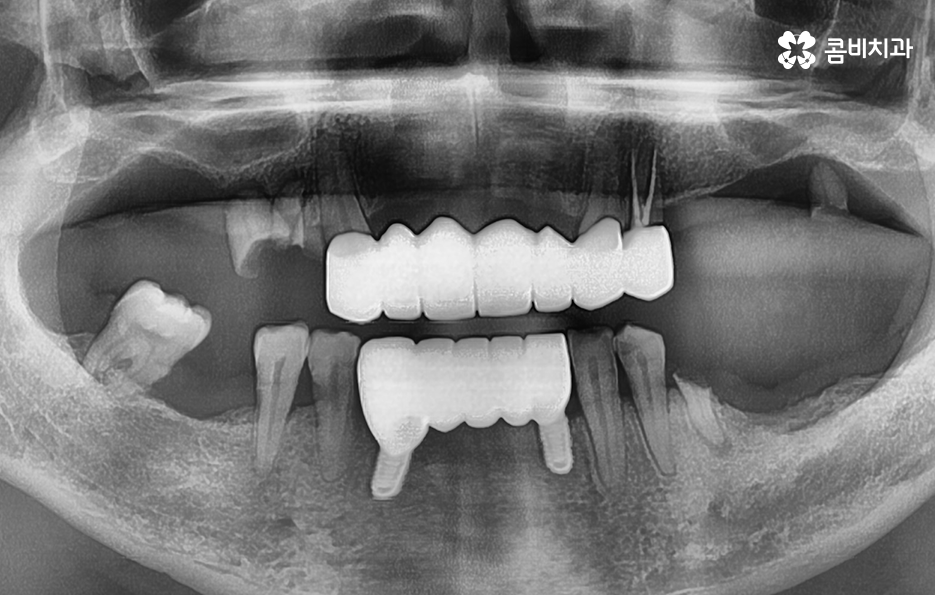

위 환자분의 엑스레이 사진을 보면 치아의 뿌리 부분에 가깝게 잇몸이 내려앉은 것을 볼 수 있는데 치아의 구조에서 뿌리쪽은 법랑질이 없기 때문에 잇몸이 내려앉고 잇몸 뼈가 치주염으로 녹게 되면 치아가 너무 아파서 식사를 하기에도 어렵고 물 한잔만 마셔도 이가 시릴 정도로 일상에 지장을 느끼실 수 있어요

결국 치아가 흔들릴 정도까지 잇몸 뼈가 녹고 치아의 뿌리도 함께 손상된다면 발치로 이어지겠지만 임플란트의 과정은 잇몸이 건강하신 환자분들과 잇몸이 약해지고 얇아지신 분들의 경우에는 치료적인 접근이 달라지기 마련인데 일반적인 임플란트의 경우 치아를 발치하고 임플란트를 올리기 까지 약 5~6개월 정도가 소요된다면 잇몸 뼈가 녹을 정도로 잇몸이 약해진 분들의 경우에는 뼈이식을 포함하여 경우에 따라서는 1년까지도 치료 기간이 걸릴 수 있기 때문에 임플란트 치료 역시도 어려운 과정을 겪게 될 수 있다는 점에서 치주염 발치의 경우 결코 가볍지 않은 시술 과정이 동반될 수 있어요

고령의 환자분들의 경우에는 잇몸 뼈의 상태 뿐 아니라 전신질환, 회복력을 함께 고려해야 하기 때문에 치료 계획에 있어서 보다 섬세하게 체크해야 하며 환자분의 잇몸 뼈 상태와 전신건강 그리고 경제적인 상황 등을 고려할 때 전체임플란트를 하게 되는 경우도 있지만 위 환자분의 사례처럼 임플란트를 최소한으로 식립하여 임플란트의 보철물을 연결하여 치아의 기능을 회복하는 경우도 있는데요